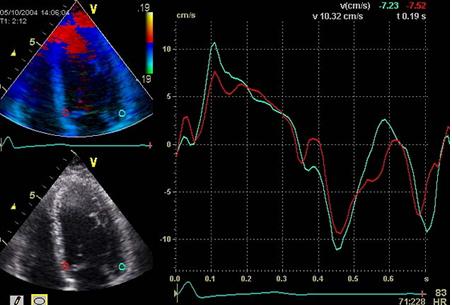

Mai concret, ecocardiografia Tissue Doppler permite evaluarea funcţiei cardiace sistolice globale prin măsurarea velocităţilor la nivelul inelului mitral şi tricuspidian, precum şi a funcţiei diastolice, prin măsurarea velocităţilor E' (velocitatea maximă diastolică precoce) şi A' (velocitatea tardivă prin contracţia atrială) la nivelul inelului mitral, respectiv tricuspidian. Velocităţile diastolice TDI reprezintă un marker al relaxării ventriculare, fiind relativ independente de presiunile de umplere. Velocităţile miocardice pot fi măsurate utilizând atât metoda Doppler pulsat cât şi Doppler color.

Imagine Doppler tisular color la nivelul peretelui septal şi lateral bazal al ventriculului stâng